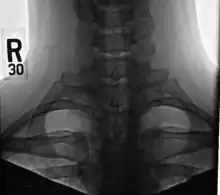

Bilateral, symmetric, full, ossified cervical ribs.

On imaging, cervical ribs can be distinguished because their transverse processes are directed inferolaterally, whereas those of the adjacent thoracic spine are directed anterolaterally.[11]